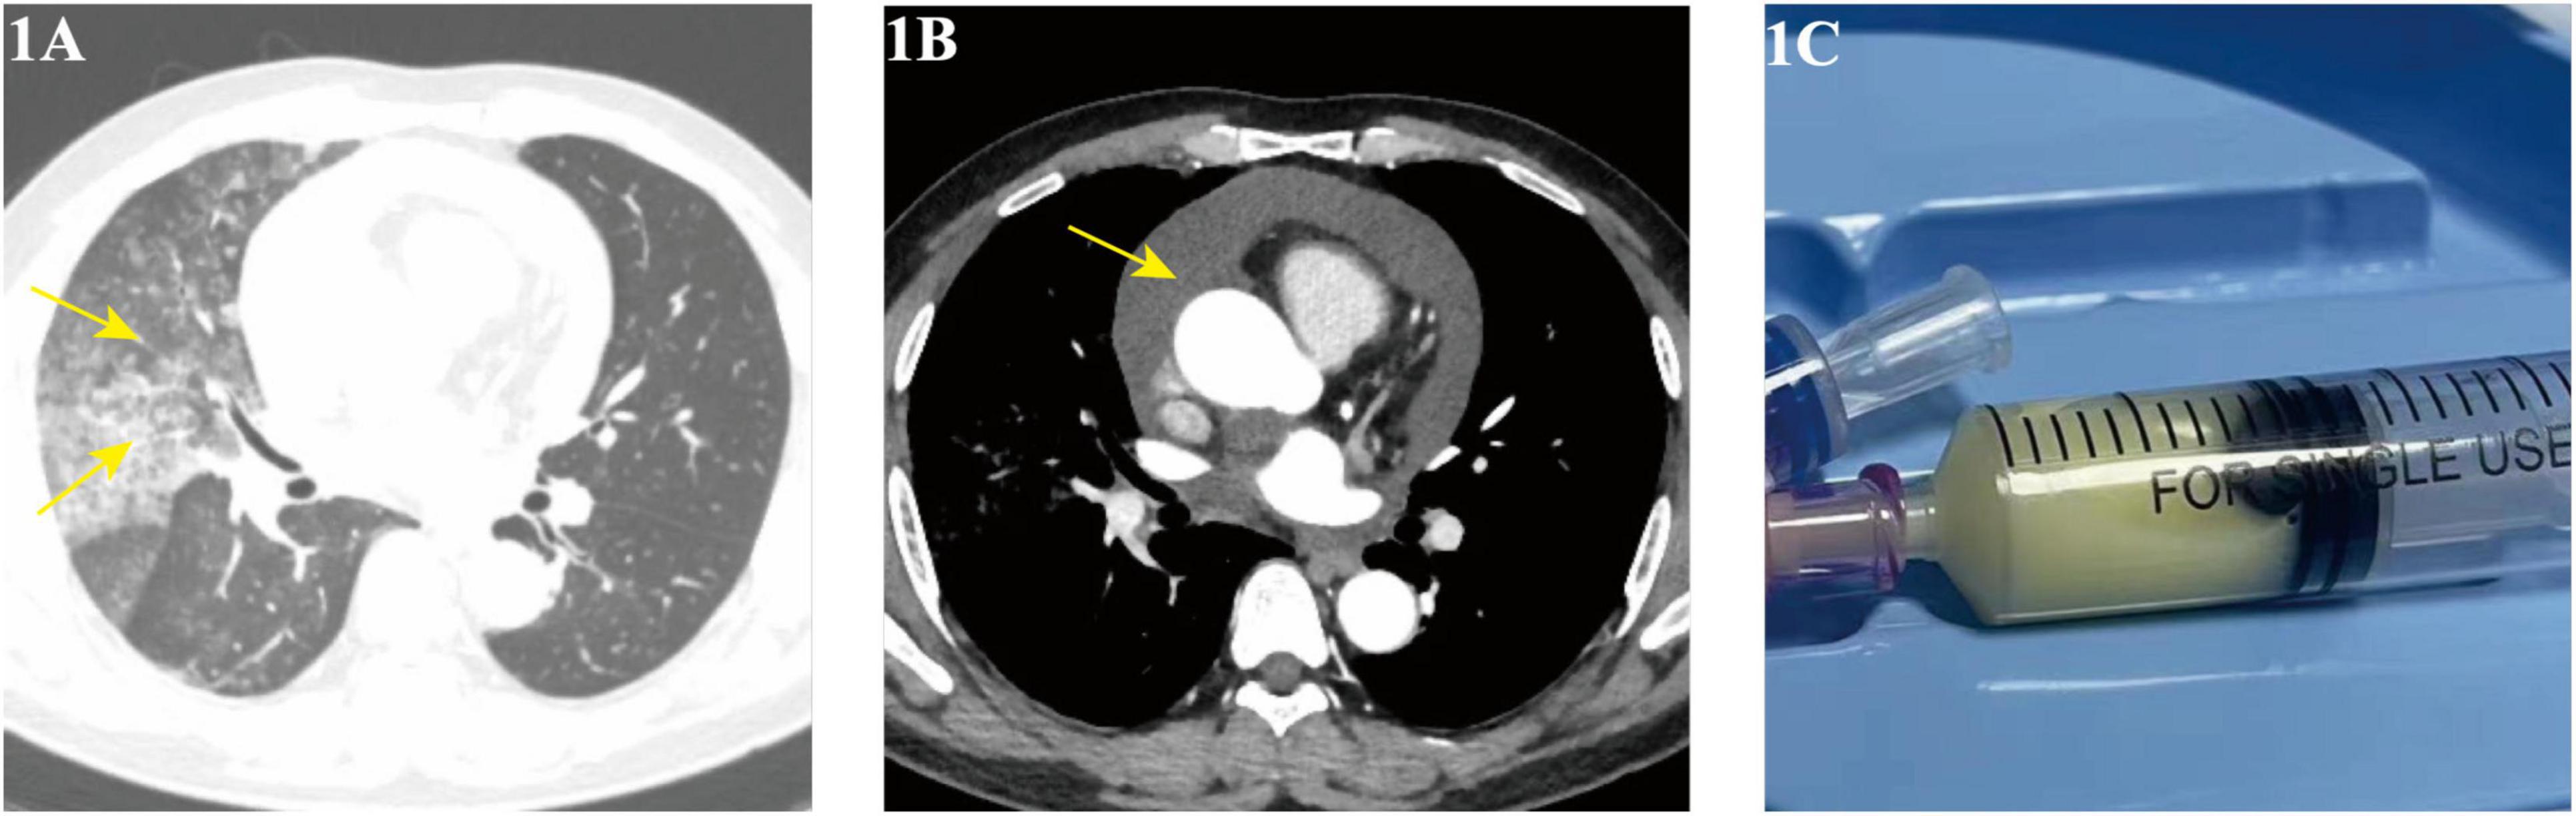

Pulmonary Lymphatic Perfusion Syndrome (PLPS) is a rare condition characterized by abnormal lymphatic drainage into the lungs, leading to symptoms such as chyloptysis and chylous effusions. We report a case of a 54-year-old male with PLPS who presented with persistent cough, milky sputum, and pericardial effusion. Following initial misdiagnosis and ineffective empirical treatment for a presumed pulmonary infection, a definitive diagnosis of PLPS was established.The patient underwent successful percutaneous thoracic duct embolization, resulting in complete resolution of symptoms and imaging findings at follow-up. This case highlights the importance of considering PLPS in patients with unexplained chylous effusions and the efficacy of lymphatic intervention as a treatment option.